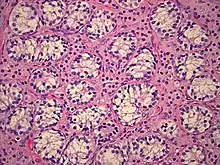

Histopathology of testicular tissue showing immature germ cells and spermatogonia with decreased tubular diameter. Scattered groups of Leydig cells appearing immature.[40]

All forms of androgen insensitivity are associated with infertility, though exceptions have been reported for both the mild and partial forms.[4][5][7][39][41][42]